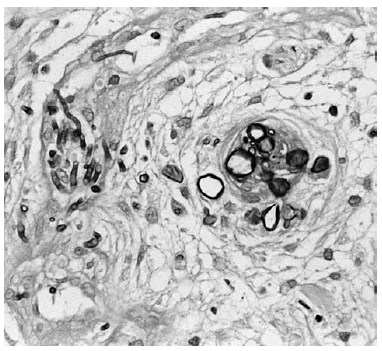

En el día +35 de quimioterapia se observaron múltiples lesiones de aproximadamente 10-12 días de evolución. Estas lesiones, papulonodulares, bien delimitadas, alguna de ellas con centro necrótico, salpicadas en tronco y miembros, eran asintomáticas y estaban infiltradas a la palpación (fig. 1). El cuadro se acompañaba de fiebre, mal estado general y debilidad muscular.

Fig. 1.--Lesiones nodulares, eritematosas, mal delimitadas, de centro necrótico en brazo.